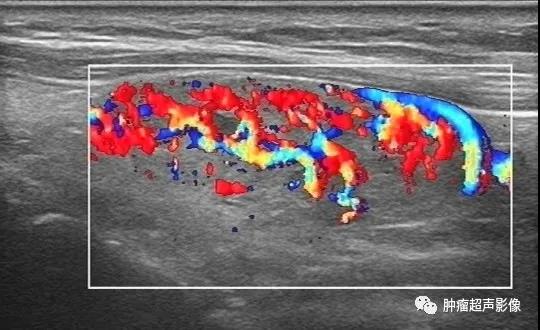

异位甲状腺(迷走甲状腺):正常甲状腺位置未见甲状腺回声,颌下见甲状腺样组织回声,回声不均,血流丰富,类似甲亢表现(推测功能不足,代偿性)